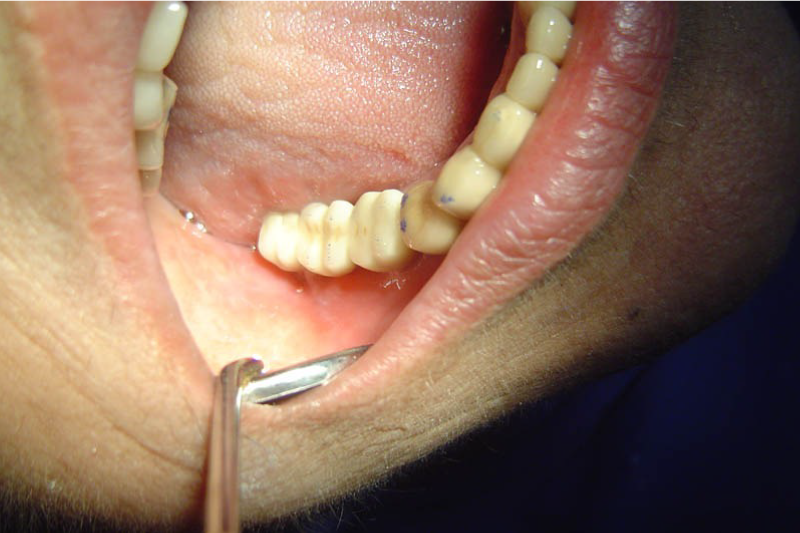

Immediate implants

Immediately after the extraction of a damaged or decayed tooth.

This approach eliminates the need for a waiting period between tooth extraction and implant placement, which is typically around 3-6 months.

Advantages – only one surgery for extraction and implant placement, early rehabilitation, preservation of bone as after extraction there is bone loss immediate implants act as a scaffold to prevent bone loss.